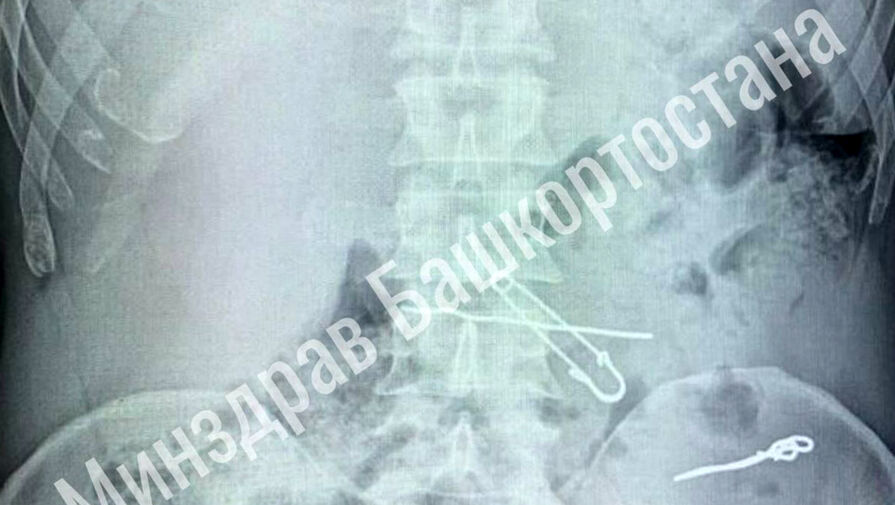

В больницу скорой медицинской помощи поступил мужчина с жалобами на сильные боли в животе. По результатам обследования выяснилось, что у него в толстой кишке находились три металлические скрепки длиной 47, 62 и 90 миллиметров, а в желудке — булавка и проволока.

Пациента срочно госпитализировали в отделение гнойной хирургии, где врачи успешно провели операцию по извлечению всех предметов. Во время вмешательства медики делали контрольные рентгеновские снимки, чтобы убедиться в полном удалении инородных тел. После операции мужчина успешно восстановился и был выписан из медицинского учреждения.